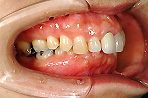

■ 叢生

| 数本の歯が歯列からはみ出て外側や内側に倒れている状態で下顎の動きを妨げている可能性があります。 |